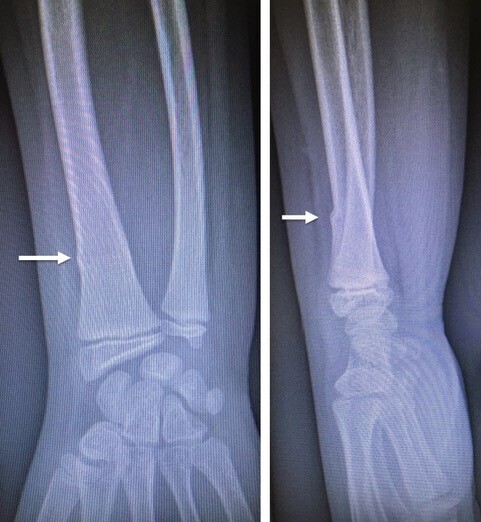

• fracture en motte de beurre : il s’agit d’une plicature plastique d’une corticale métaphysaire (fig. 3) ;

• fracture en bois vert : une corticale est pliée mais continue alors que l’autre est rompue (fig. 4) ;

• fracture « plastique » ou « arcuature » : il n’y a pas de fracture mais une courbure plastique s’étendant sur toute la longueur de l’os (fig. 5) ;

• fracture sous-périostée (fracture « en cheveu ») : l’os est fracturé, non déplacé, et le périoste est intact. Chez l’enfant jeune, ce périoste assure la solidité ; les enfants peuvent parfois marcher malgré une fracture du fémur ou du tibia. Le diagnostic est porté sur une boiterie et une douleur à la pression osseuse. La radiographie initiale est souvent normale. Parfois, on devine un trait fracturaire. Ce n’est que quinze jours à trois semaines plus tard qu’un cal osseux apparaît, prouvant ainsi rétrospectivement l’existence de cette fracture sous-périostée ;

Il y a, par exemple, un fort potentiel de remodelage des fractures du quart inférieur des deux os de l’avant-bras.

Leur diagnostic est aisé, habituellement par la réalisation de radiographies simples. Certaines fractures ont des spécificités pédiatriques liées à la moindre résistance osseuse (fracture en bois vert, fractures en motte de beurre ou fractures plastiques) ou à la présence de cartilages de croissance (fractures-décollements épiphysaires).

Il existe des fractures propres à l’enfant : fracture en motte de beurre, fracture en bois vert, fracture sous-périostée, fracture plastique et fractures touchant le cartilage de croissance. La classification de Salter et Harris permet de classer ces fractures et de donner, dès l’accident, un pronostic en matière de risque de trouble de croissance.